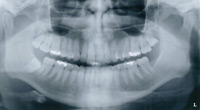

Full Mouth Periapicals

The most complete periodontal x-ray exam is the full mouth periapical exam. Each film shows the entire tooth and surrounding bone, in detail, and allows the periodontist to see subtle change occurring in the bone support. Root canal problems around the root tips are also easily seen. Generally 16-18 films are exposed. It is recommended that patients who have had moderate or advanced periodontal disease have full periapical x-rays every three years. In addition, bitewings are suggested every 6-12 months to check for decay.